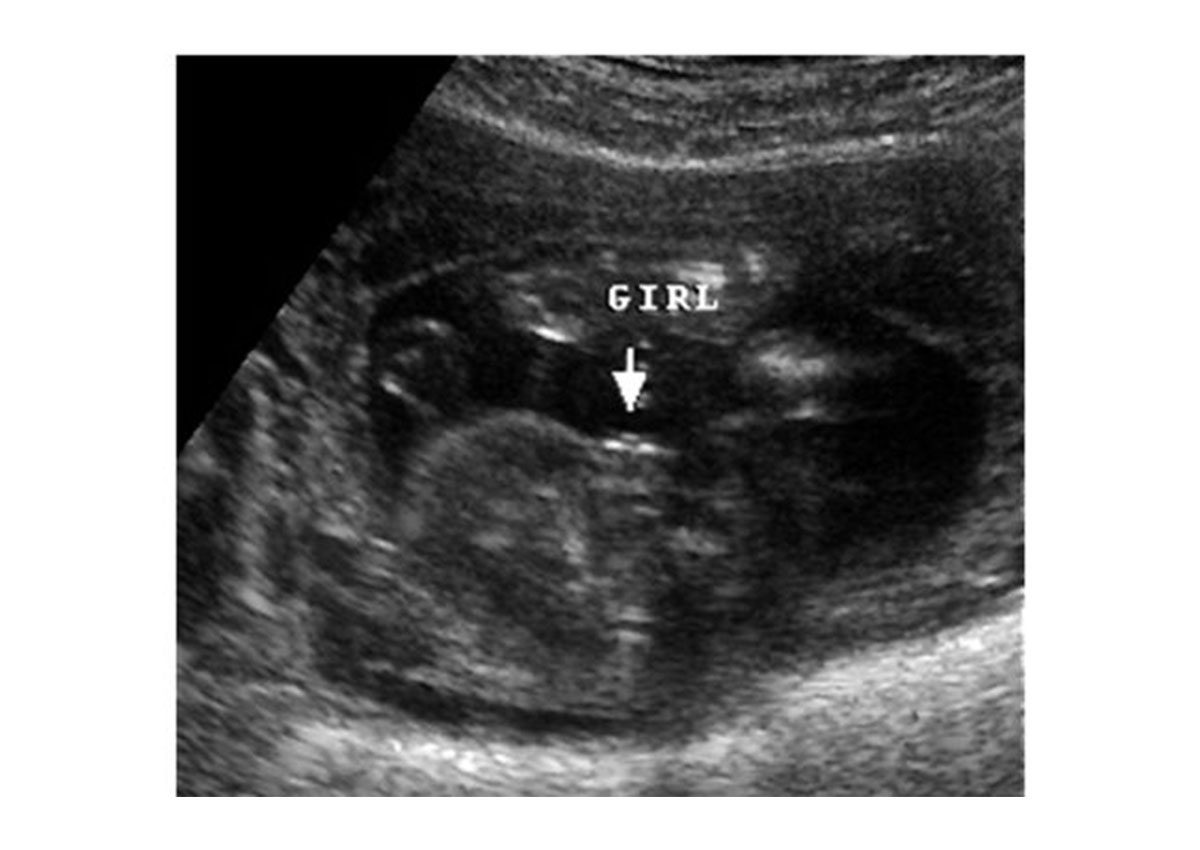

ولتحديد جنس الجنين يتم النظر الى الجهاز التناسلي، فإذا ظهر على الشاشة ثلاث خطوط بيضاء، يدل هذا ان الجنين انثى، أما اذا كان الجنين ذكر، فيُعرف هذا بشكل واضح من العضو التناسلي ومن الكرتان الصغيرتان اللتان تمثلان العضو التناسلي للذكر.

الجنين الانثى